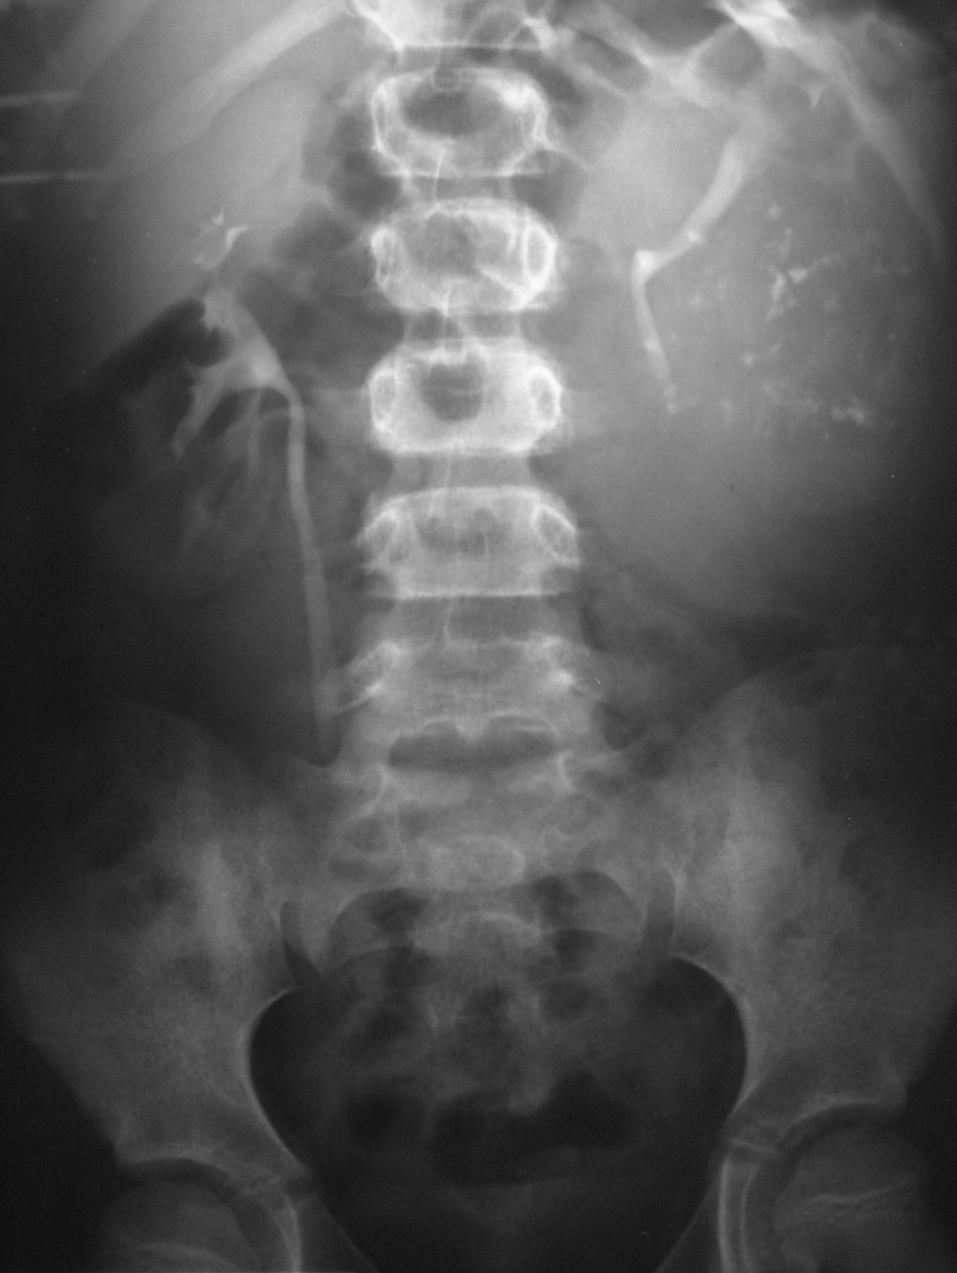

De los pacientes diagnosticados de carcinoma de células renales (n= 4) (con edad y presentación mostrados en la tabla 2) en dos casos se localizaron masas renales en la corteza renal, con infiltración del sistema pielocalicial. De estos dos, uno demostró fuga de contraste del sistema excretor en la radiografía abdominal post-TC con contraste, y el otro invasión de médula con extensión hasta el uréter proximal (fig. 5). En un único caso se apreciaron abundantes calcificaciones grumosas intratumorales dispersas (fig. 6).

Fig. 6. Carcinoma de células renales. Urografía intravenosa que muestra una masa en hemiabdomen izquierdo, con abundantes calcificaciones grumosas dispersas, que desplaza el sistema pieloureteral.